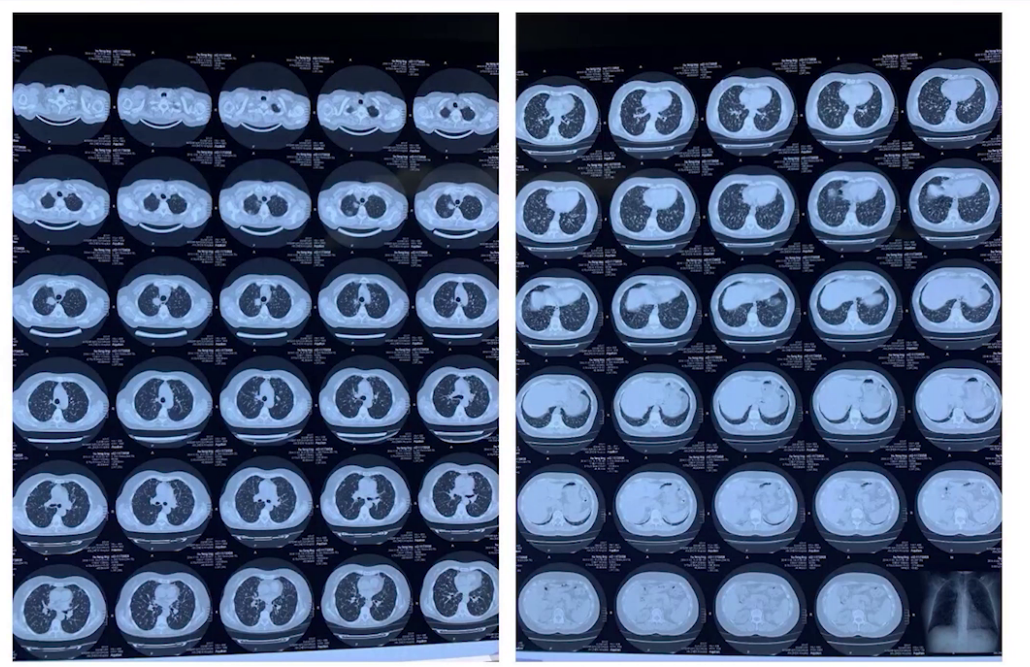

2015年3月,患者症状突然加重,外院复查胸部CT示右肺上叶肿物直径达3.1cm,双肺结节及纵隔多发淋巴结肿大,腹部CT提示右侧肾上腺肿物,考虑髓样脂肪瘤可能性大,全身骨扫描未见转移征象。

2024.11.2 外院胸部CT:

2025.3.2 外院胸部CT: